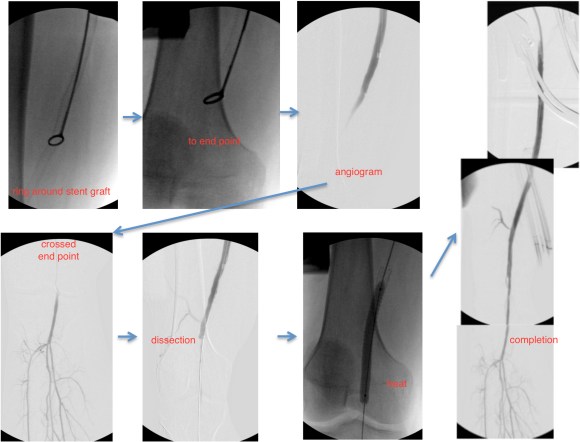

The patient’s right common femoral artery was exposed in the usual manner. Wire access across the occluded external iliac artery was achieved from a puncture of the common femoral artery. Remote endarterectomy (EndoRE) was performed over a wire from the common femoral artery to the external iliac artery origin (pictures below).

The 18F sheath went up with minimal resistance, and the EVAR was performed in the usual manner. The left common iliac artery occlusion was managed percutaneously from a left brachial access. The stent graft on the left was terminated above the iliac bifurcation and a self expanding stent was used to extend across the iliac bifurcation which had a persistent stenosis after recanalization.

The patient was operated on in a hybrid endovascular OR suite. A right groin incision was made to expose the common femoral artery for endarterectomy and left common femoral access was achieved for angiographic access, but also to place a wire across the occlusion into the common femoral artery.

All actions on the external iliac artery plaque are done with an up-and-over wire, allowing for swift action in the instance that arterial perforation or rupture occur. This event is exceedingly rare when the operation is well planned. With this kind of access, an occlusive balloon or repairing stent graft can be rapidly delivered.

The common femoral endarterectomy is done from its distal most point and the Vollmer ring is used to mobilize the plaque. A Moll Ring Cutter (LeMaitre Vascular) is then used to cut the plaque.

The plaque is extracted and re-establishes patency of the EIA.

The plaque end point is typically treated with a stent -in this case, the common iliac plaque was also treated.